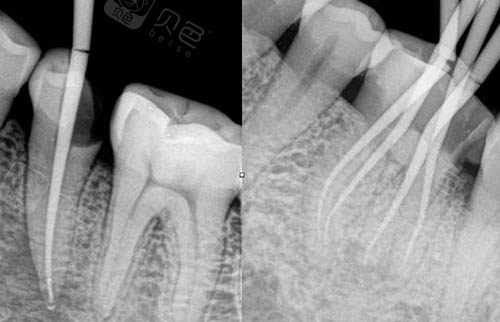

根管填充图示

根管治疗ct照片

牙齿根管治填充